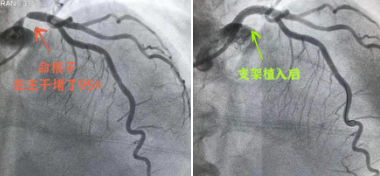

冠脉造影检查的结果让betway在线登陆张瑶俊博士心血管工作室的常尚主任倒吸了一口凉气,“病根找到了,患者左主干堵了95%,立刻手术,恢复血管供血!”

生死悬于一线,进导丝、球囊扩张、支架植入、高压后扩张……快速、精准、熟练,手术一气呵成,李奶奶左主干严重病变的的血管供血恢复了。手中李奶奶未感不适,术后安返病房,李奶奶心慌胸闷的症状明显改善了。